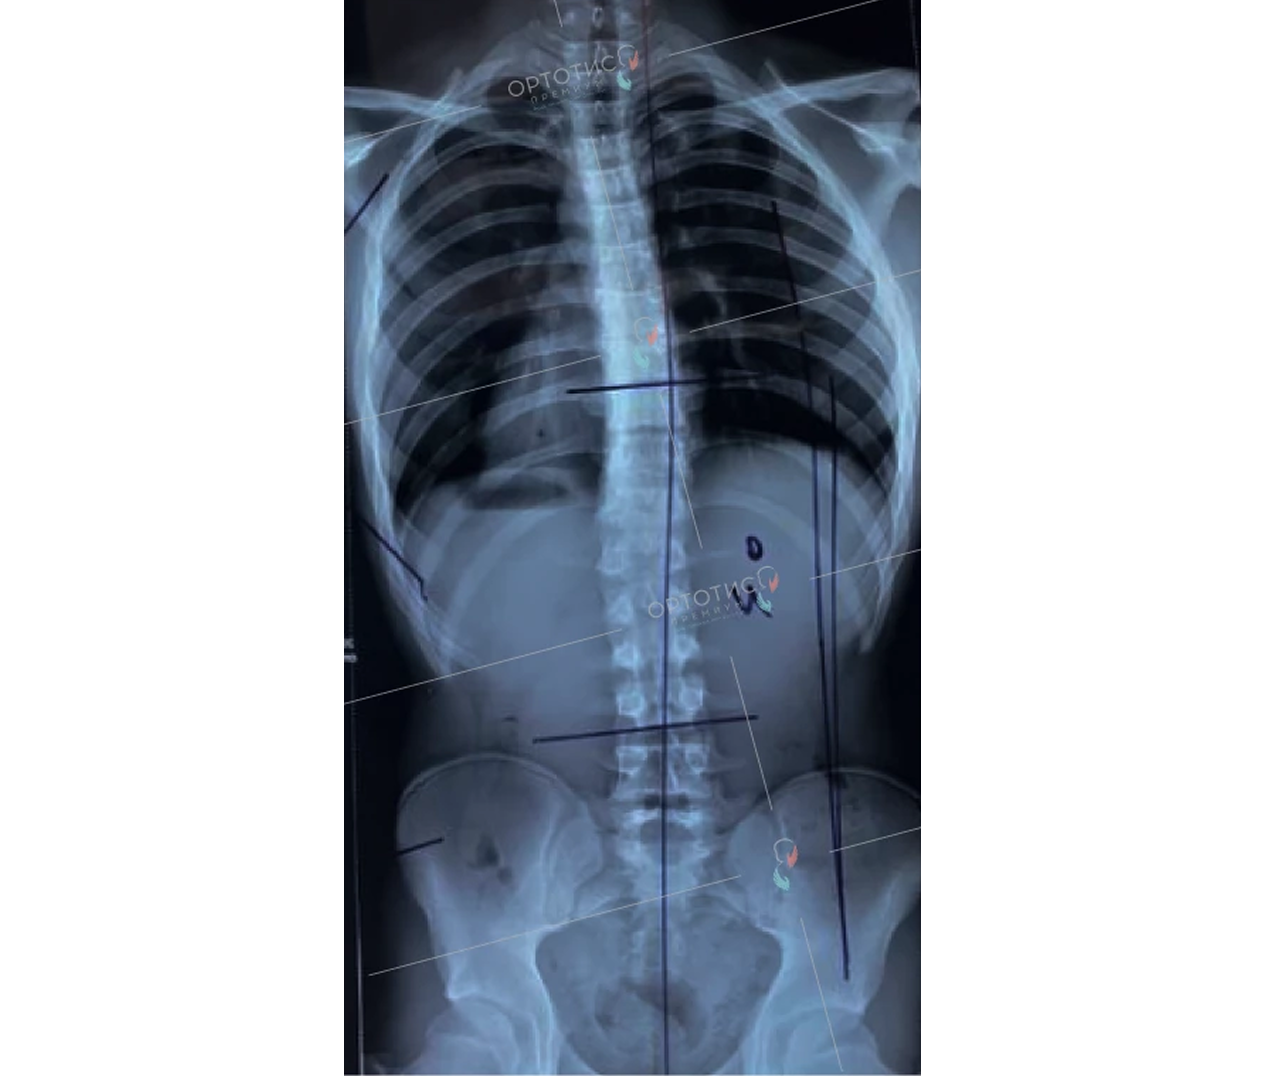

Корсет Шено в Алматы: эффективное лечение сколиоза

Корсет Шено — это «золотой стандарт» в лечении сколиоза у детей и подростков. В клинике Ортотис Центральная Азия в Алматы мы изготавливаем активные ортопедические корсеты, которые не просто удерживают позвоночник, а эффективно исправляют деформацию.

• Идиопатический сколиоз с углом искривления от 20° по Коббу;

• Быстро прогрессирующие формы деформации позвоночника;

• Кифосколиоз и другие нарушения осанки.

Мы используем высокоточное 3D-моделирование, что позволяет создать корсет, идеально соответствующий анатомии ребенка. Это обеспечивает максимальную коррекцию при сохранении мобильности. Наши техники-ортопеды в Алматы проводят регулярную коррекцию изделия по мере исправления позвоночника.